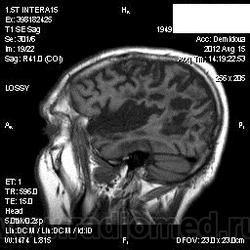

Мои собственные наблюдения.

1 случай -локальная гемиатрофия.2 случай-диффузная.

Молодой человек после автомобильной аварии.3 года лежит.Двигаются только глаза.Зрелище душещипательное.

Евгений, конечно же, мои случаи не являются "чистой" атрофией-согласна.Мне пока не встречались случаи болезни Пика, Альцгеймера и другие "чистой воды" атрофии.Второй случай- состояние после длительной комы вследствие автодорожной травмы 3 года назад.Пациент проходил исследование в прошлом году , в этом родители привезли на динамику.